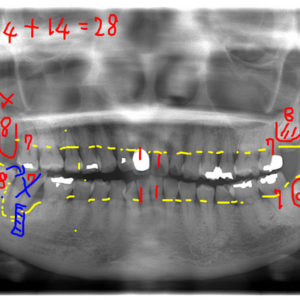

左上3番目の歯がなかなか生えてこないということを主訴に来院された子供さん(13歳)です。 レントゲン写真にて歯の位置を確認しました所、2番目の歯の下に位置しており、かなり方向がずれていることが判明しました。 そこで埋伏歯 […]